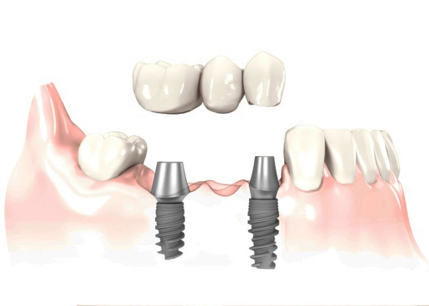

Puente sobre implante.

¿Cómo funciona¿ Anclando al hueso de la mandíbula dos implantes de titanio que harán la función de la raíz, dándole soporte a la masticación.

Una vez introducidos los implantes, se fijan las tres piezas dentales, fabricadas en metal y cerámica, igualando el color con los dientes vecinos para brindar un aspecto natural y saludable.